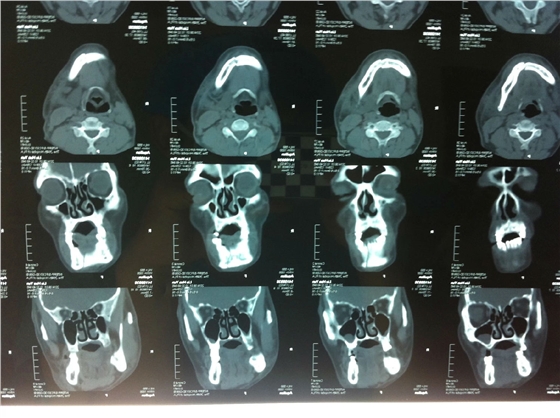

患者男性,主因左面部反復(fù)腫脹半年余,就診后行全景片檢查,發(fā)現(xiàn)下頜骨多發(fā)性囊腫,初步診斷為多發(fā)性頜骨囊腫綜合征,安排住院手術(shù)。

入院后全麻下手術(shù)治療,左側(cè)下頜骨囊腫較大,術(shù)前考慮病理性骨折可能,準(zhǔn)備鈦釘鈦板固定,術(shù)中摘除囊腫后,發(fā)現(xiàn)下頜骨下緣骨量尚可,未給予固定。術(shù)后病理診斷為下頜骨角化囊腫,考慮到患者可能為基底細(xì)胞癌綜合征,術(shù)中切除頸部皮膚痣兩處,術(shù)后病理診斷為:皮膚痣,排除基底細(xì)胞癌綜合征?;颊哂凶髠?cè)第六肋骨分叉肋,綜合以上特征,最終診斷為多發(fā)性頜骨囊腫綜合征。